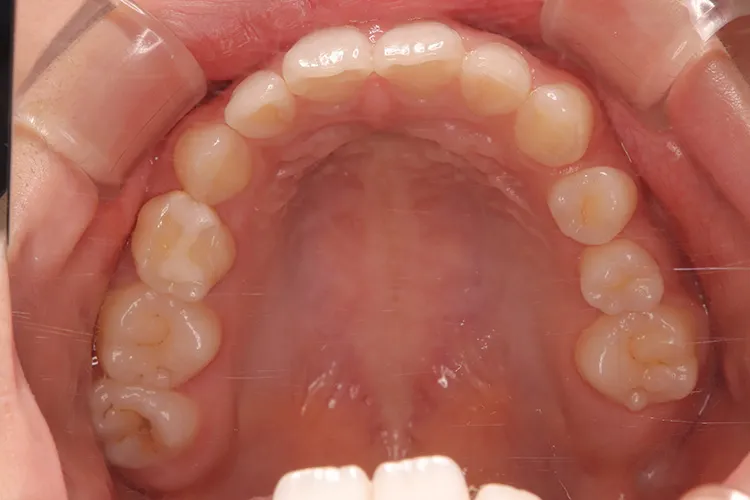

症例9/

永久歯先天欠如

- 治療期間

- 3ヶ月

- 費用

- 147万円(税込)

治療前

治療後

レントゲン画像

治療内容

20歳の患者様の永久歯先天欠如のケースです。右上4・右下5・左下45の他、第二大臼歯も3本先天欠如していました。年齢も若いため、歯を傷める可能性の高いブリッジは選択されず、長期間安定して機能するインプラントを選択されました。このように若年者で永久歯が先天欠如しているケースにも応用できます。